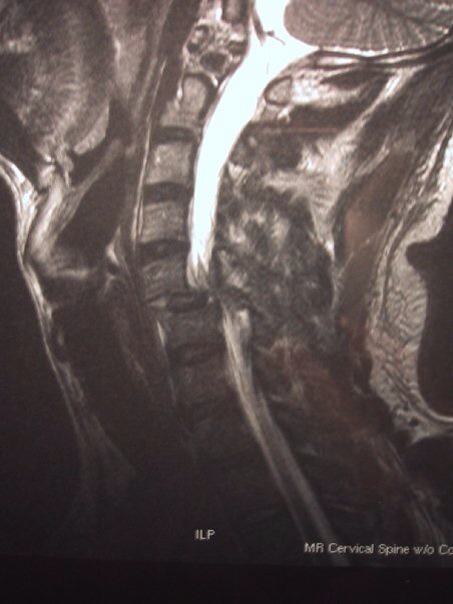

Being a Navy SEAL was a job he loved, but after 8 years, his career was cut short by a freak parasailing accident on the Chesapeake Bay. His head hit the water hard, and he was dragged through the water as his wife watched helplessly from the beach. He stayed conscious and did everything he could to keep calm and stay positive. But the dislocated neck and crushed spinal cord left him little ability to move, and doctors at the Richmond VA Medical Center questioned whether he’d ever walk again.